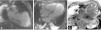

These findings prompted reversal of oral anticoagulation and suspension of antiplatelet therapy. Cardiac magnetic resonance imaging (CMRI) was performed to clarify the anatomy and aid the planning of surgical repair, which confirmed the presence of a large pseudoaneurysm and showed its extension and close relation to the right ventricle, which was subject to significant compression. Delayed enhancement study was able to define the extent of the infarct and documented the presence of viable myocardium in the mid-basal segments of the left ventricle (Figure 5).

Cardiac magnetic resonance imaging, steady-state free precession sequences in vertical long-axis (A) and 4-chamber (B) views, confirming the presence of a large left ventricular pseudoaneurysm. Delayed enhancement images (phase-sensitive inversion recovery) acquired 10minutes after administration of gadolinium, in 4-chamber view (C), show a transmural area of contrast uptake surrounding the aneurysm (arrows).